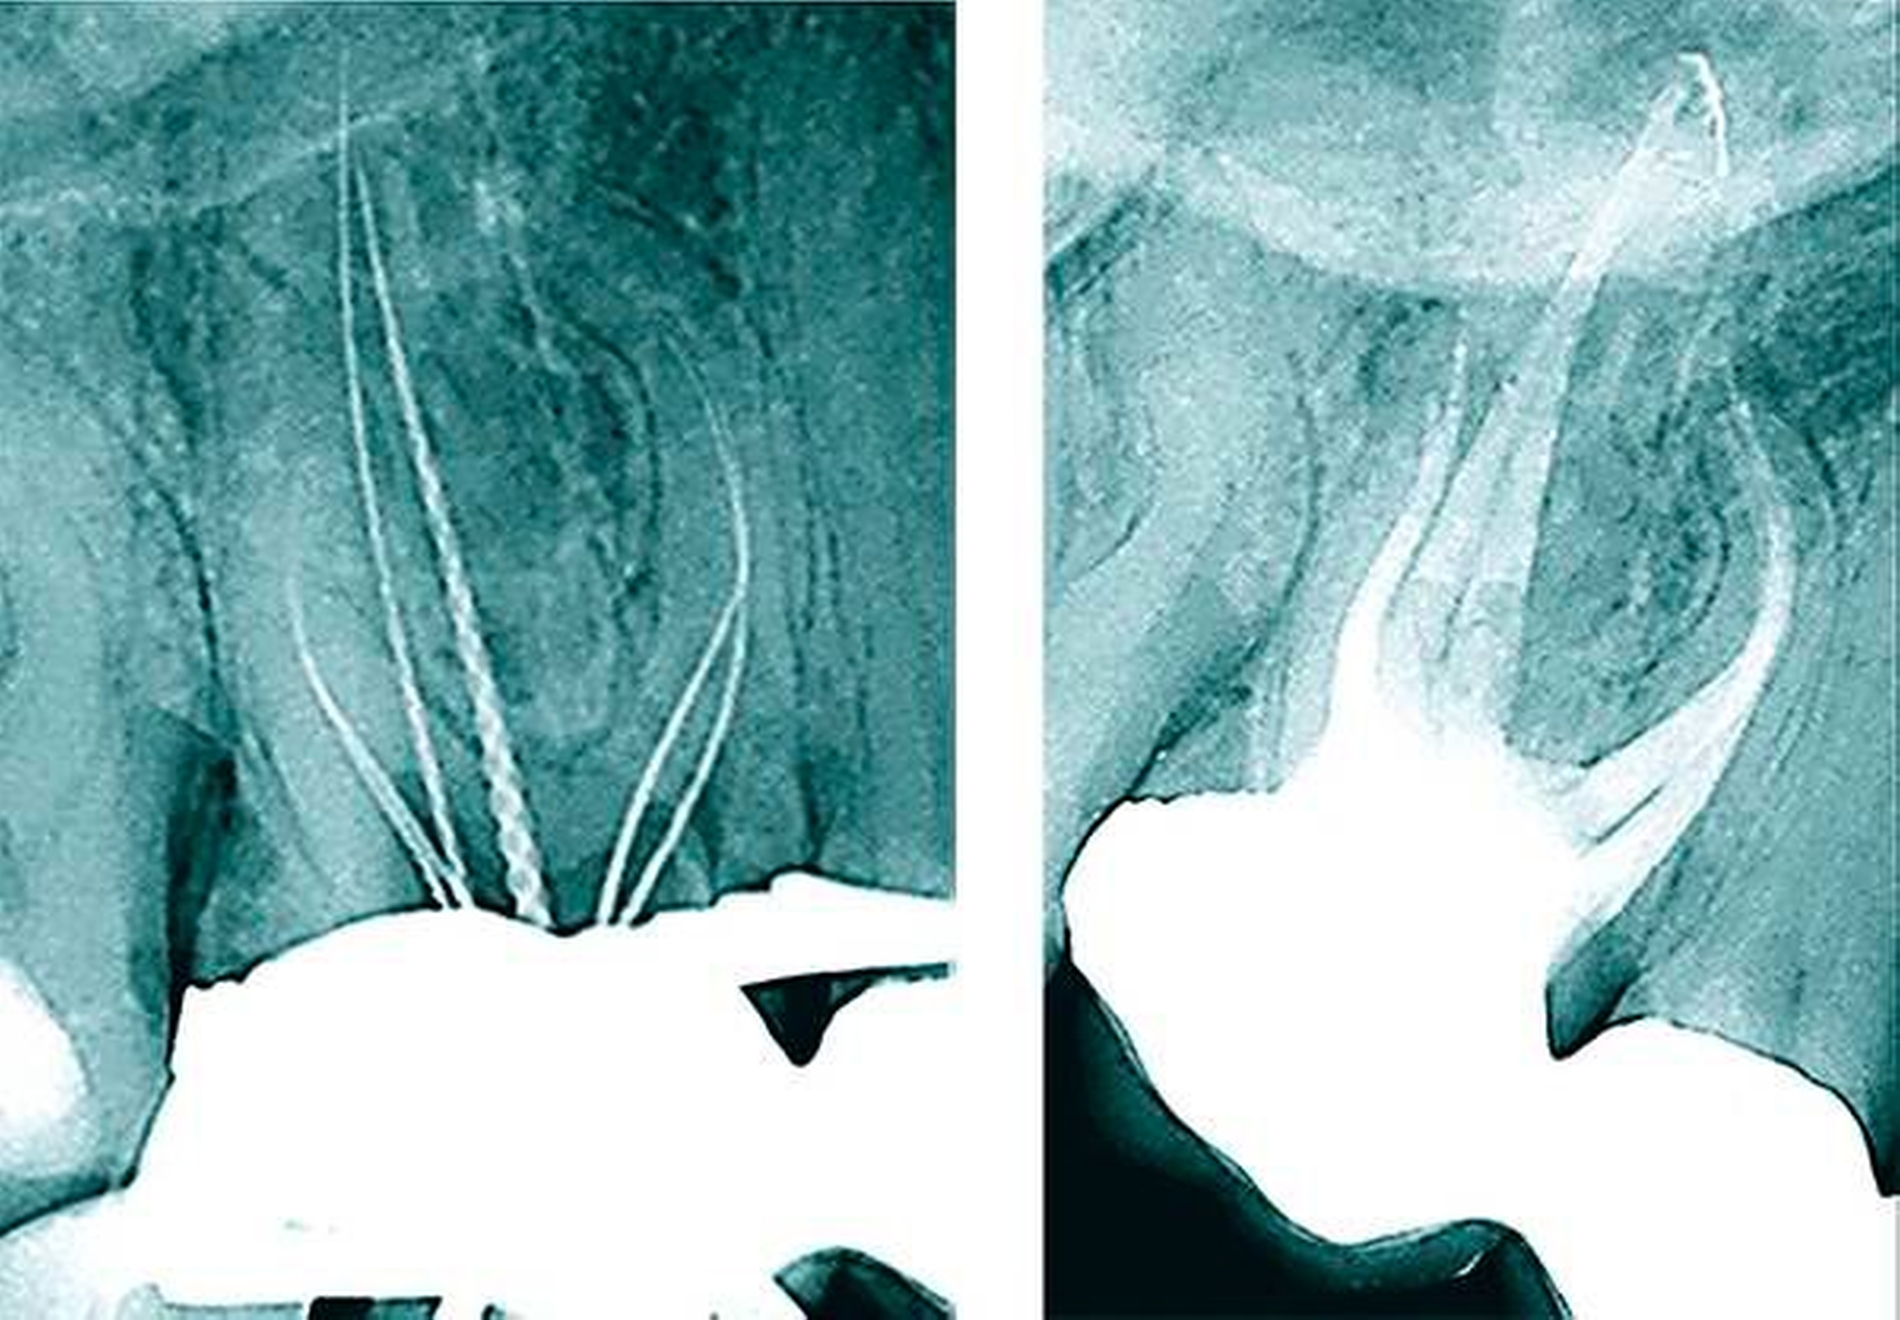

Eine besondere Schwierigkeit ist das Auftreten x-förmiger Wurzelkanäle (Typ VI nach Vertucci) in der mesiobukkalen Wurzel oberer erster Molaren [Arnold & Paqué, 2010]. Die Konfluenz der beiden mesiobukkalen Wurzelkanäle MB1 und MB2 im mittleren Wurzeldrittel ist häufig ein Hinweis auf eine erneute Aufteilung im apikalen Wurzeldrittel. Das Erschließen des erneuten Abzweigs gelingt nach einer minimalinvasiven sonoabrasiven Präparation vom MB1 unter Nutzung eines Dentalmikroskops (Abbildungen 12 und 13). Seltener sind diese Aufteilungen an distobukkalen Wurzelkanälen zu beobachten (Abbildung 14).

Das Auffinden des MB2 bei oberen zweiten Molaren kann sich erheblich unterscheiden (Abbildung 3). Insbesondere bei bandförmigen Fusionen der mesiobukkalen und der palatinalen Wurzel bestehen mehrere Möglichkeiten des Wurzelkanalzugangs. So kann man auch in seltenen Fällen den zweiten mesiobukkalen Wurzelkanaleingang im koronalen Wurzeldrittel des palatinalen Wurzelkanals auffinden (Abbildungen 17 und 18, Abbildung 3).